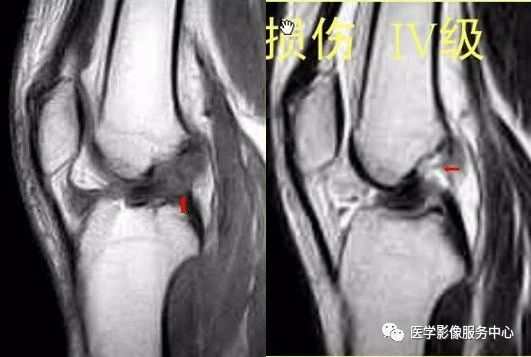

股四头肌腱

股四头肌肌腱:有四组肌肉末端集中插入髌骨上极组成三层的股四头肌肌腱;各层正常可在矢状位图像上清晰显示,表现为带状的均匀低信号,各层中间有高信号脂肪分隔;最常表现为光滑的三层结构,而两层或四层表现不常见;正常的股四头肌肌腱平均厚度为6-10mm、平均宽度月28-42mm。

正常股四头肌腱

大多数撕裂发生在或靠近肌腱的髌骨上极插入部。部分撕裂表现为肌腱任意层的中断,常类及股直肌部分。全层撕裂表现为肌腱的完全断裂和局部水肿、出血引起的肿块,在T2和IR序列图像上表现为高信号。完全撕裂时多数可见因为肌肉收缩引起的肌腱末端退缩,髌骨的位置可下移。

股四头肌腱撕裂